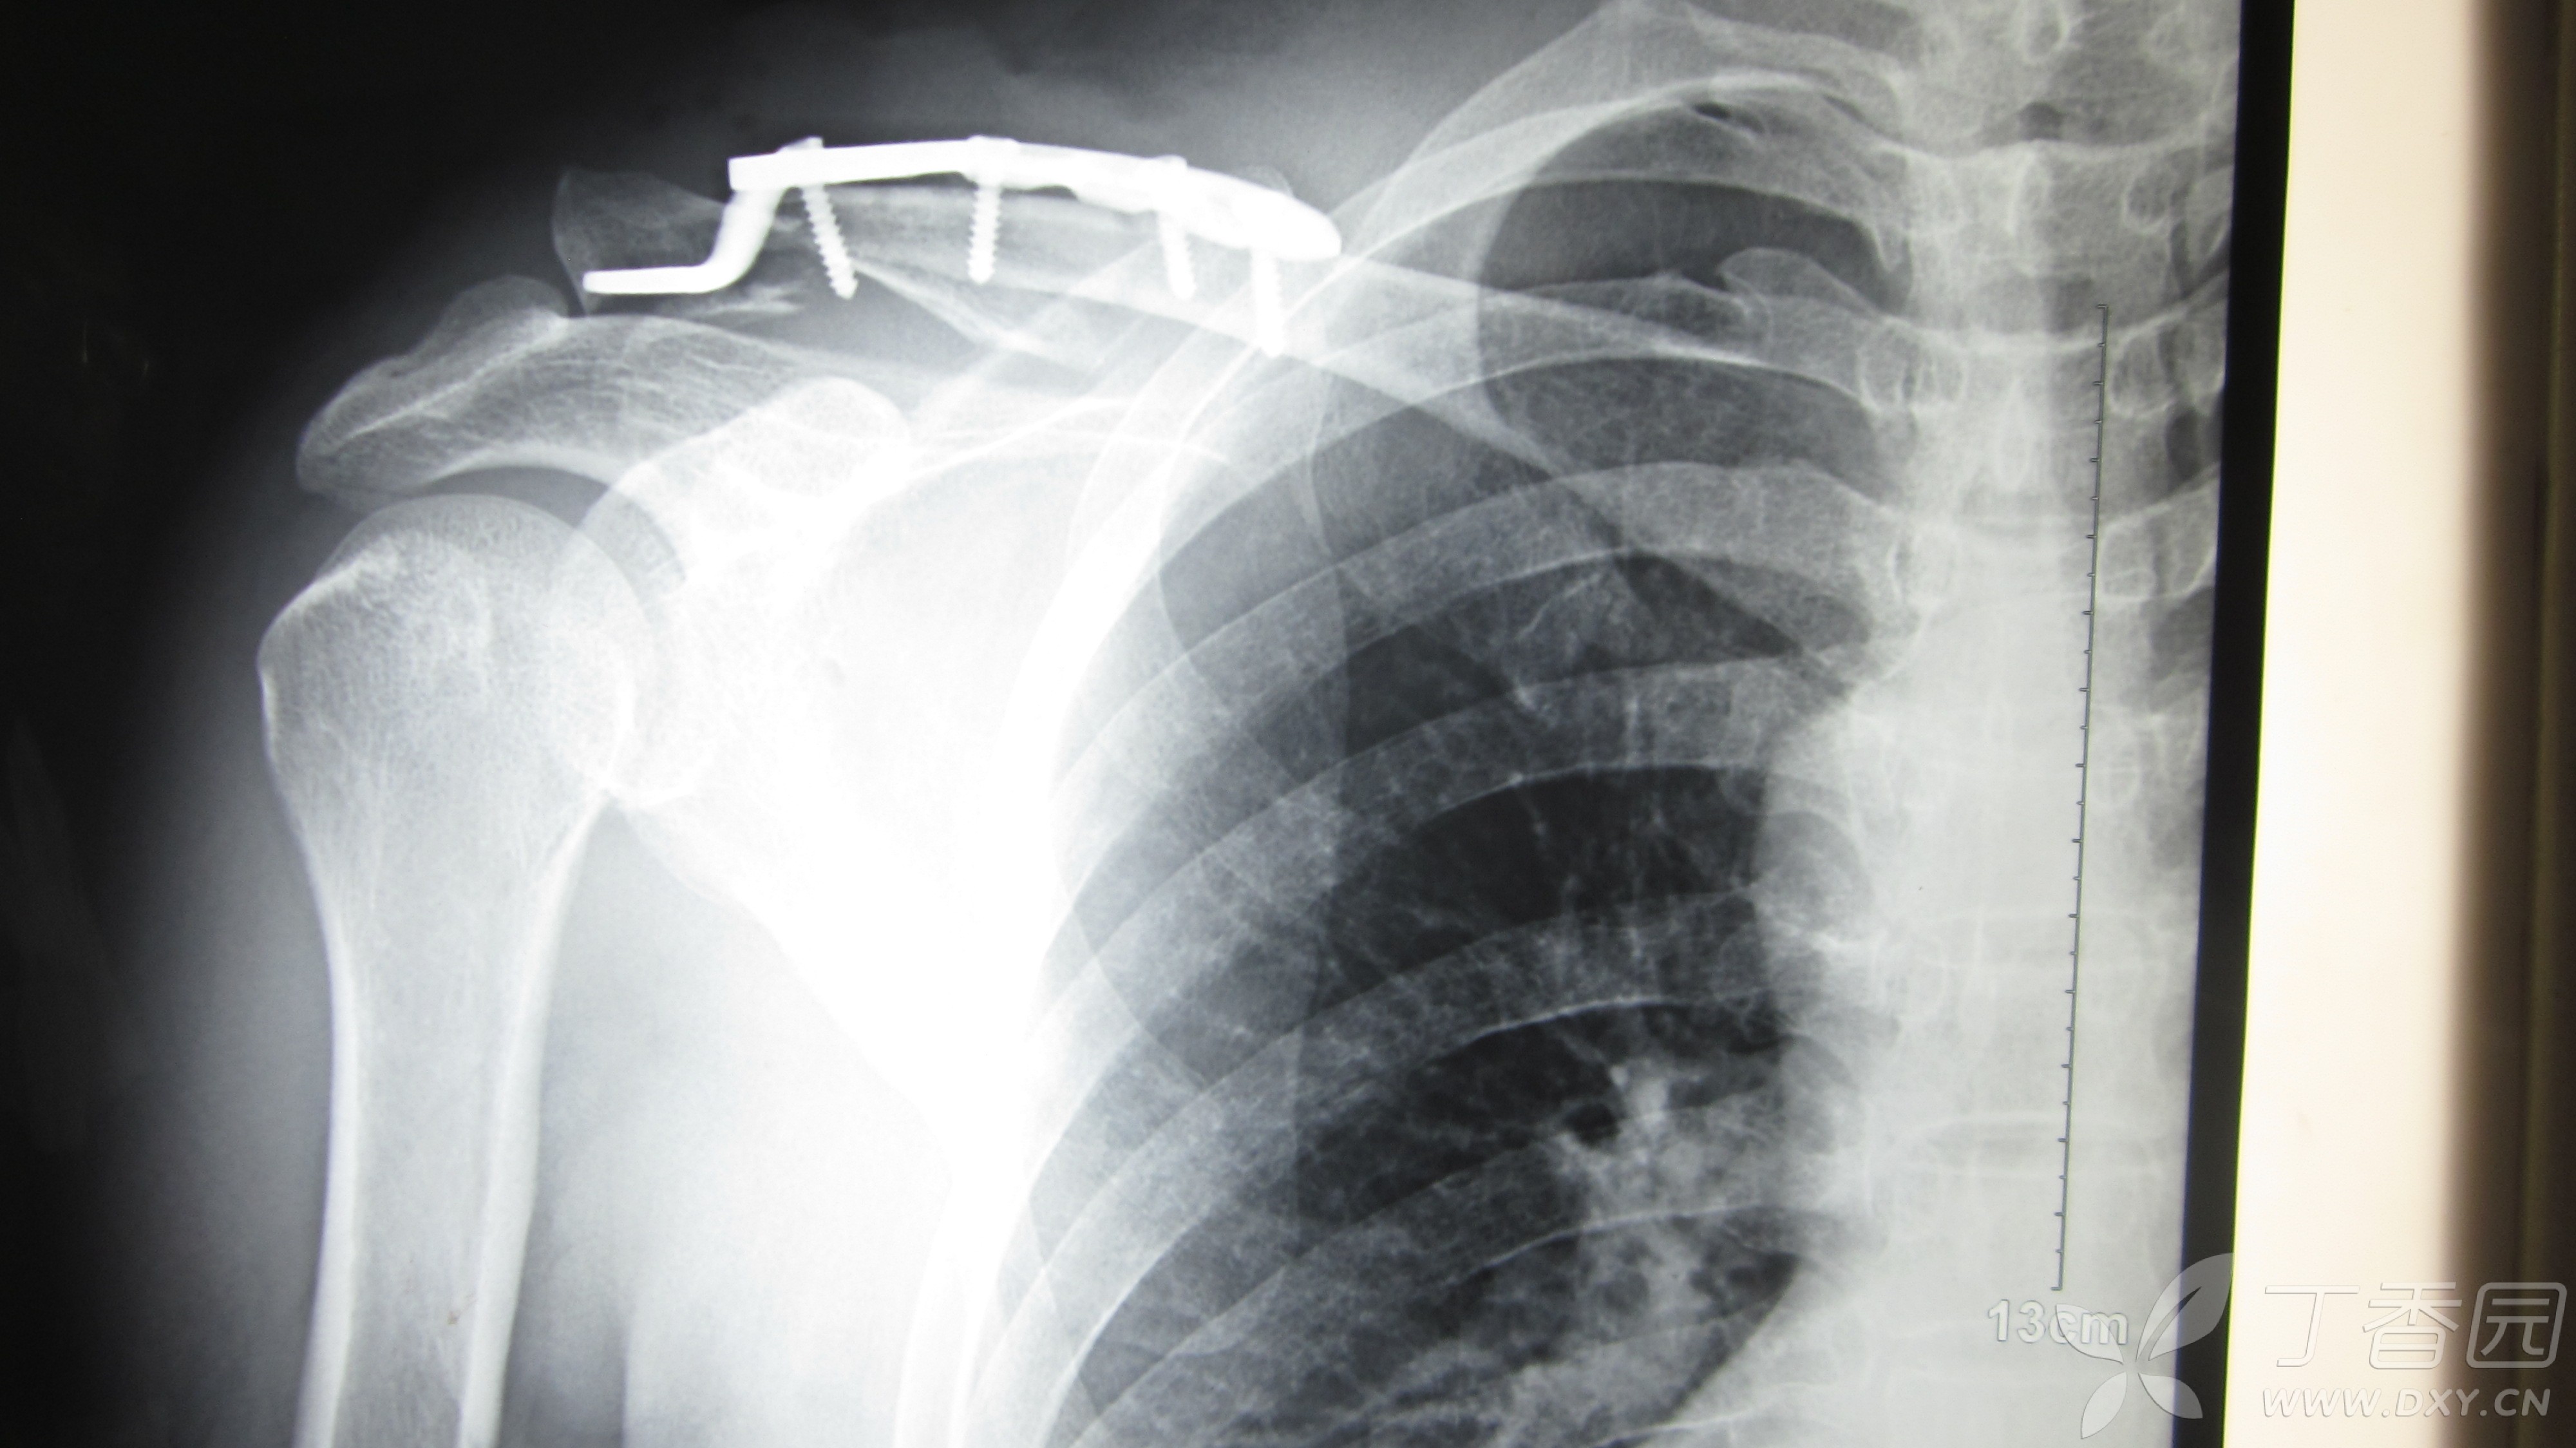

丁香园论坛

图片尺寸4000x2248